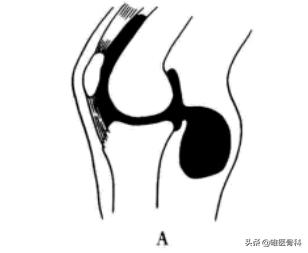

腘窝囊肿多位于腓肠肌腱和半腱肌肌腹内侧弯处,是由于原发或继发性关节腔压力升高,关节液经后关节囊薄弱区膨出形成囊肿。

囊腔经股骨内髁后方约4~24 mm 的水平状裂口与膝关节腔相通。腘窝囊肿是这一类疾病的总称,不属于肿瘤,更不会恶变或者转移。

当这些关节疾病引起关节囊内压增高时,关节液会自水平状裂口流出,使滑囊膨大。

而这种裂口存在着一种类似于单向阀的机制,关节液进入囊内的单向流通十分容易,而由囊内反流入关节腔则十分困难。